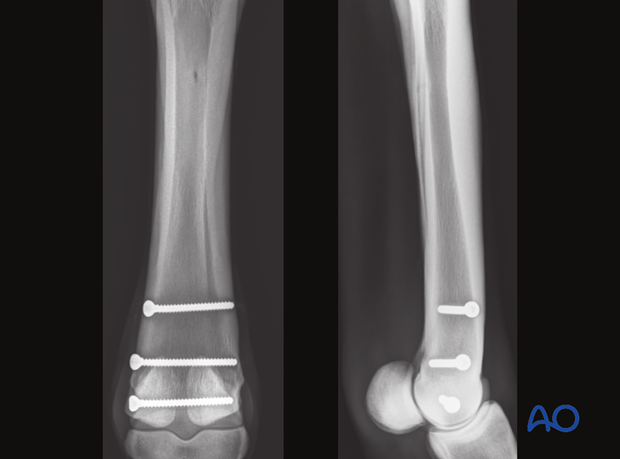

Additional screws may be added according to the radiographically visible length of the fracture. In standing horses, however, most surgeons place only 2-3 screws.

NEVER place a screw where you cannot clearly see the fracture line.

Follow up radiographs are usually taken 90 days postoperatively and again before returning to training.